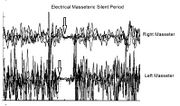

| 09:18, 4 June 2023 | Post Root-MEPs.jpeg (file) |  |

108 KB | Gianni | 1 | |

| 09:17, 4 June 2023 | Pre Root-MEPs.jpeg (file) |  |

884 KB | Gianni | 1 | |